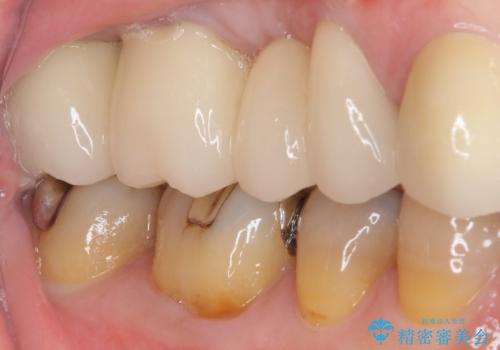

処置後はオールセラミックブリッジにて補綴し、再発防止のために就寝時にナイトガード(マウスピース)を装着していただくこととしました。

術後に痛みの続く処置を2度も受けていただくこととなりましたが、処置後は出血などの気になる症状がなくなり、患者様には大変満足していただきました。